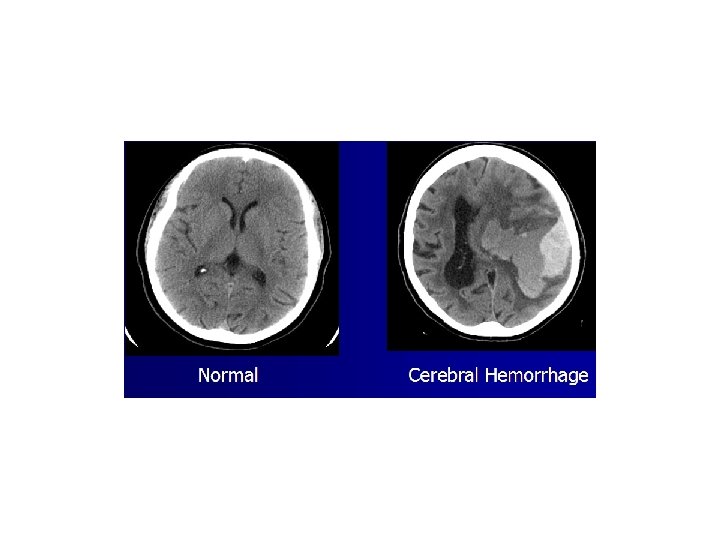

Causes of Brain Death • • • Cerebral anoxia Cerebral hemorrhage Subarachnoid hemorrhage Trauma Meningitis